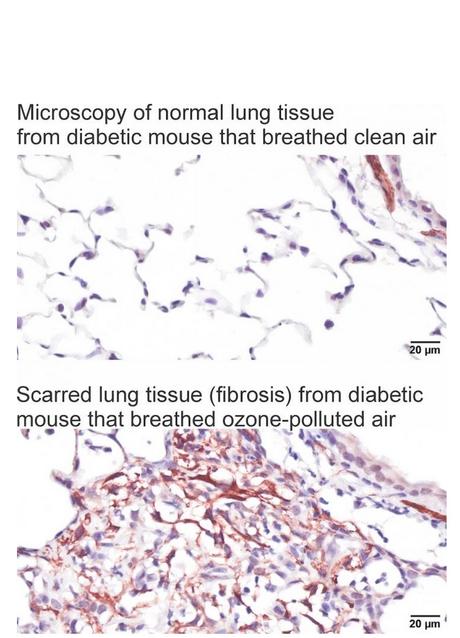

L’étude, menée sur des souris en bonne santé, des souris présentant une résistance à l'insuline légère et des souris présentant une résistance à l'insuline sévère, confirme

- une relation directe entre les niveaux de résistance à l'insuline et la gravité de l'inflammation et de la fibrose pulmonaires ;

- les souris diabétiques se montrent particulièrement sensibles à l'inflammation et au remodelage tissulaire causé par une exposition répétée à l'ozone.

Ces données, chez l’animal, confirment que l'exposition à l'ozone pourrait exacerber la fibrose pulmonaire, en particulier chez les personnes diabétiques et un diabète mal contrôlé, peut aggraver des lésions pulmonaires.